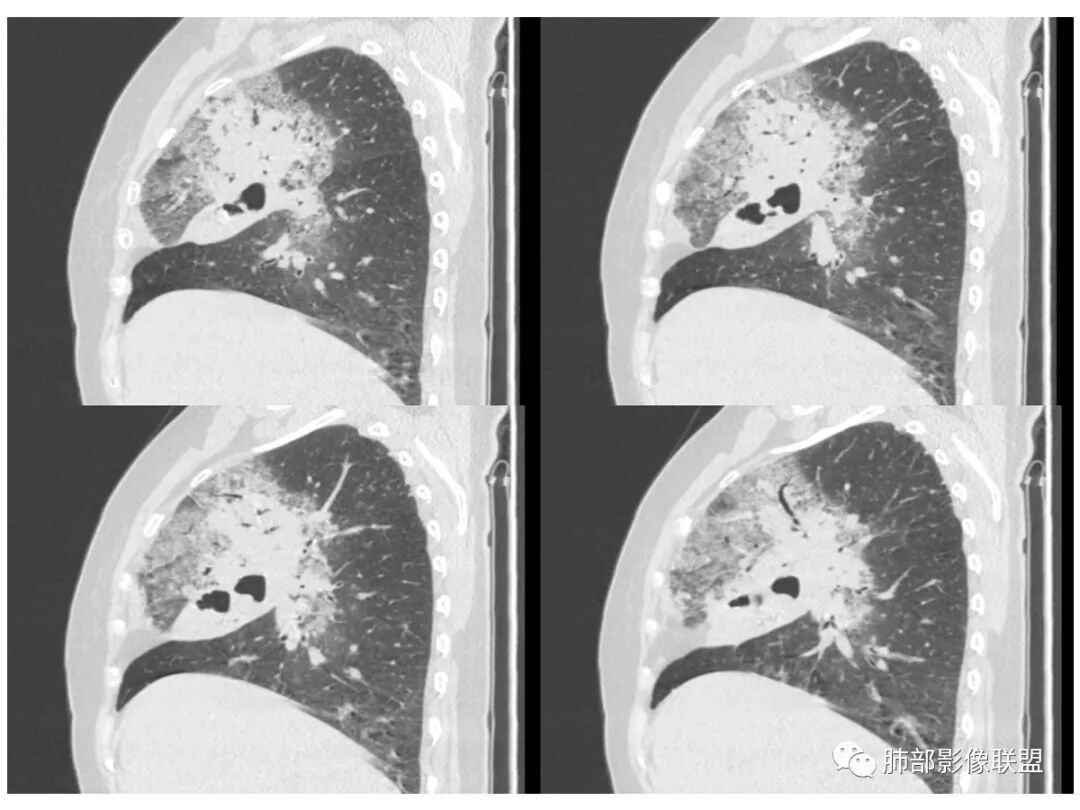

右肺上叶大片状阴影,内见僵硬的支气管,部分支气管轻度扩张,内见一空洞和液平,病灶边缘可见磨玻璃影,首先考虑恶性病变,粘液性腺癌伴感染可能。

老年女性,右肺上叶大片实变及磨玻璃密度影,磨玻璃边缘清晰,内可见小叶间隔增厚,内可见空洞,似可见分隔,叶间裂局部膨隆,纵膈窗,没有增强,枯树枝不明显,肺炎型肺癌可能,鉴别大叶性肺炎,结核?

老年女性,慢性病程,咳嗽伴白色粘液痰,无发热腹痛,糖尿病,白细胞及C反应蛋白不高,血沉快,铁蛋白高。胸部CT,右肺上叶大片状实变伴磨玻璃密度影,边界不清,边缘局部膨隆,叶裂弧形下坠,实变影宽基底与胸膜相贴;右肺下叶前基底段见类似病灶;右肺中叶不张并空洞形成,空洞内见气液平面;综合考虑右肺上叶及下叶肺炎型肺癌,右肺中叶结核。

老年女性,病史1月,右肺上中叶大片状影,跨叶,上叶为主,磨玻璃为主,边界模糊,部分实变,内见空洞影和液气平面,壁光滑,支气管开口狭窄,局部有扩张,右肺门淋巴结钙化,首先考虑感染性病变,结核可能,鉴别粘液腺癌。

老年女性,亚急性起病,右肺上中叶大片状影,跨叶,上叶为主,磨玻璃为主,边界模糊,部分实变,内见空洞影和液气平面,壁光滑,洞内可见结节形成,局部有扩张,首先考虑感染性病变,结核可能;洞内可见结节样病灶,鉴别合并曲霉、肿瘤。

患者老年女性,亚急性起病,胸部CT:右肺上叶大片实变,可内见坏死性空洞,可见mGGO,GGO边缘清晰,局部彭隆,内见支气管充气征,可惜没增强,粘液腺癌要考虑,但病灶明显是内朝外不支持,综合考虑结核,建议查痰找抗酸杆菌、气管镜

老年女性,咳白色粘液痰,右肺跨叶大片高密度影,密度不均匀,其内见支气管枯树征,有空洞,边缘部分清楚,叶间裂有下坠膨隆感。考虑粘液腺癌,鉴别干酪性肺炎

我觉得这个长轴和支气管平行,不是和胸膜平行。不是起源于胸膜下,病灶比较密实,内部粘液密度不多,这是不符合地方。当然也有很恶性的特点,

这些层面的支气管我觉得像结核的狭窄后扩张,